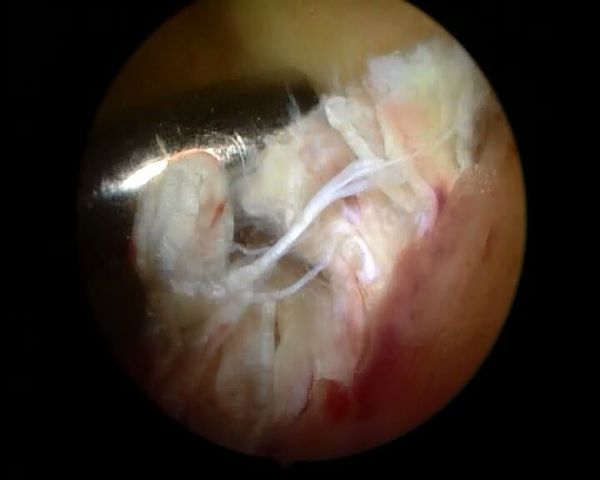

关节镜微创手术治疗前交叉韧带断裂患者!!!

600x480 - 18KB - JPEG